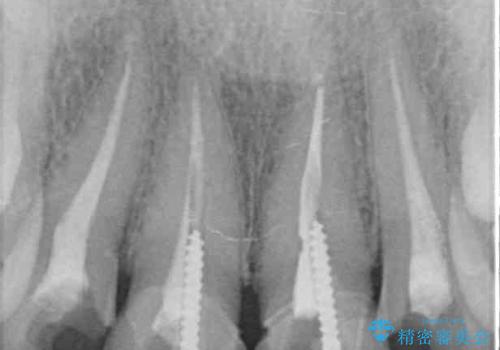

- 前歯のクラウンの変色や歯の変色を気にして来院された患者様です。

グラスファイバーを用いた土台により歯質を強化した上で、オールセラミッククラウンにて補綴することとしました。